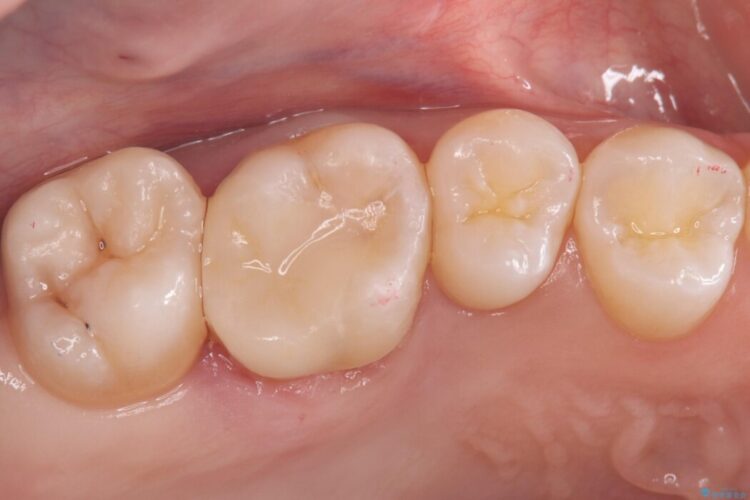

右上奥歯が欠けてしまい来院されました。

右上6番の舌側が欠けてしまっている状態でした。

破折リスクを考慮し、セラミックアンレーで治療を行うこととしました。